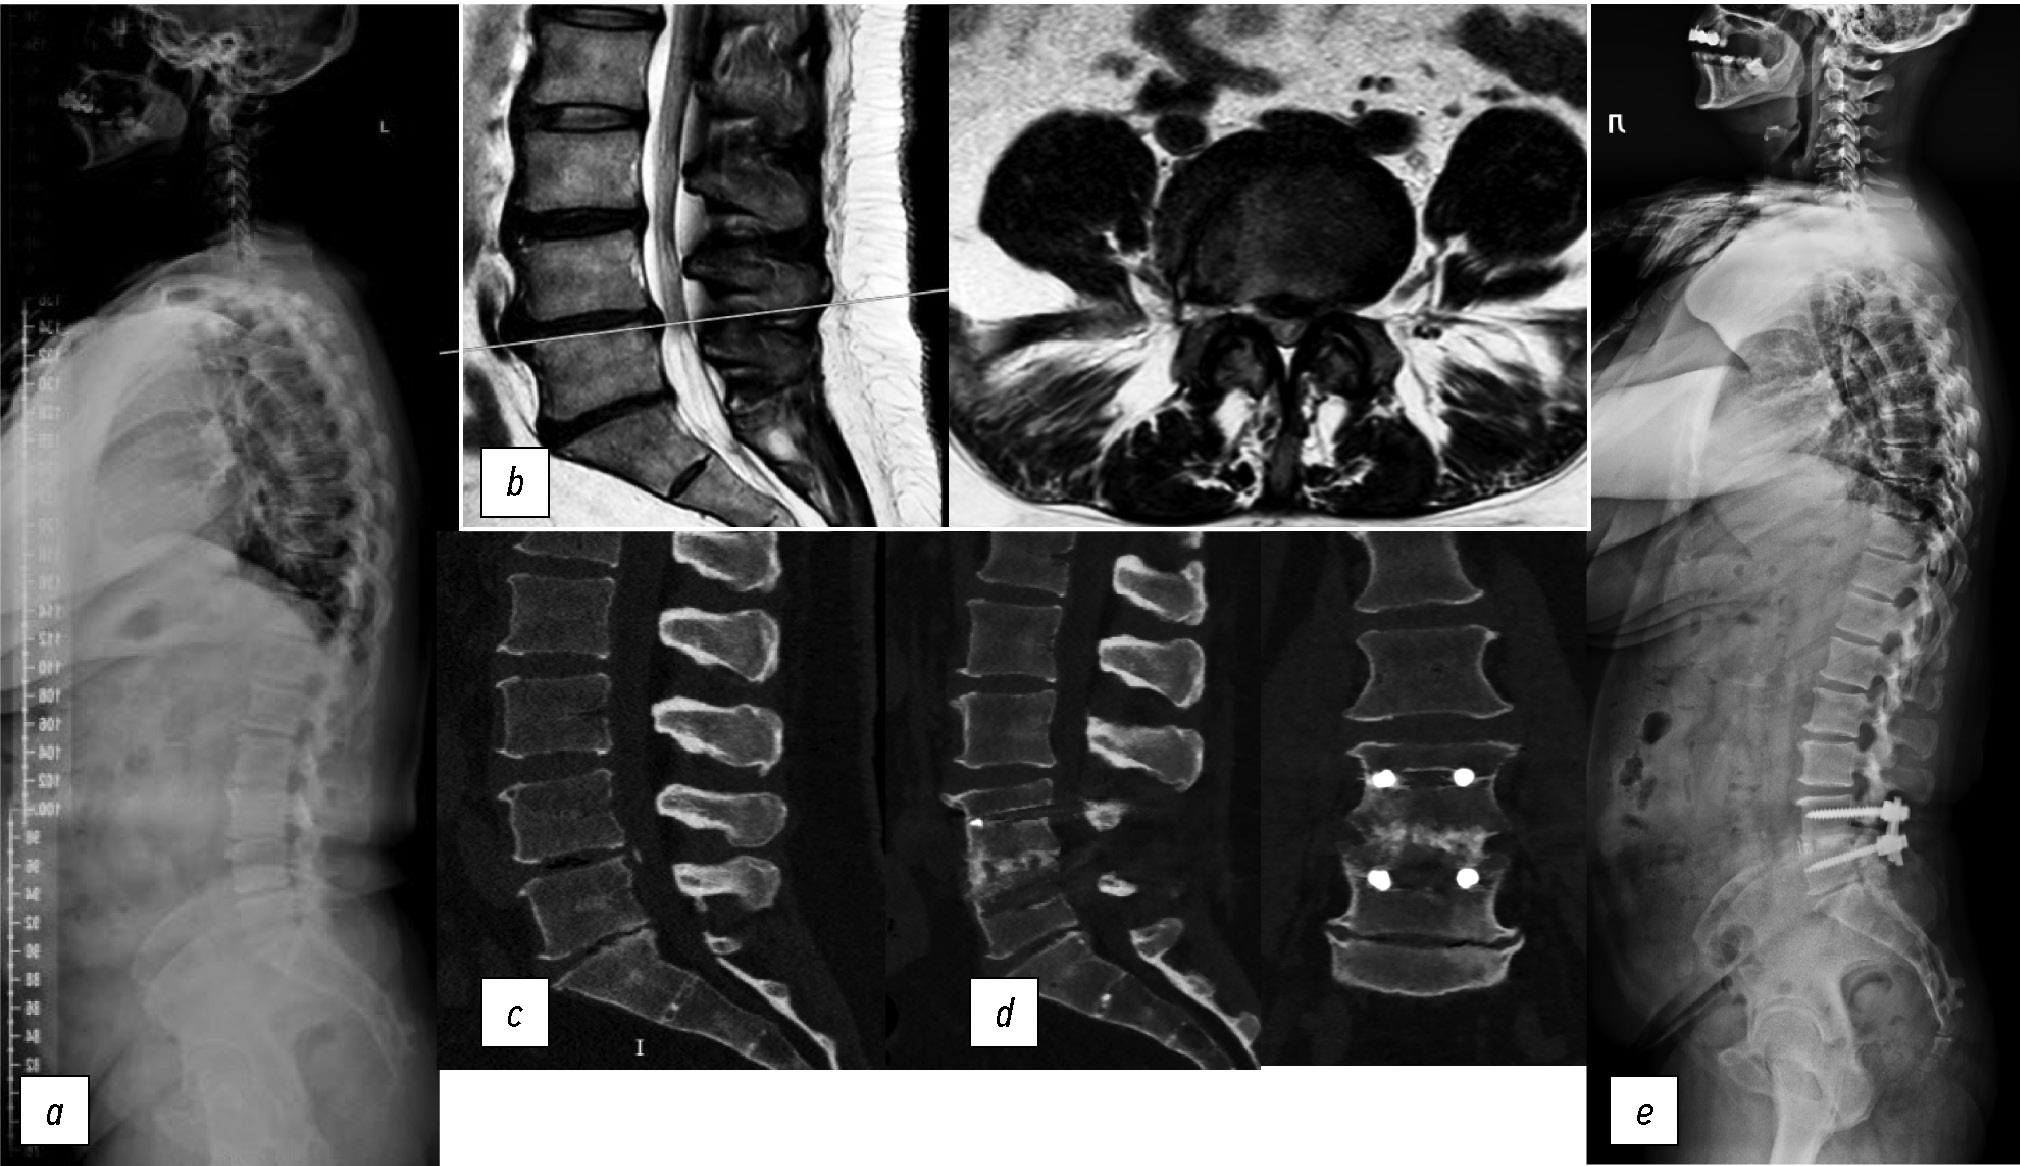

В качестве иллюстрации приводим клинический пример из нашей практики (рис. 1).

Рис. 1. Пациентка Г.: a — постуральная рентгенография позвоночника в боковой проекции перед операцией, b — МРТ поясничного отдела позвоночника в сагиттальной и аксиальной проекциях до операции, c — КТ поясничного отдела позвоночника в сагиттальной проекции перед операцией, d — КТ поясничного отдела позвоночника в сагиттальной и фронтальной проекциях после операции, e — постуральная рентгенография позвоночника в боковой проекции после операции.

Fig. 1. Patient G.: a, preoperative standing lateral radiograph of the spine; b, preoperative sagittal and axial MRI of the lumbar spine; c, preoperative sagittal CT of the lumbar spine; d, postoperative sagittal and coronal CT of the lumbar spine; e, postoperative standing lateral radiograph of the spine.

Пациентка Г., 1968 г.р. Распространённые дегенеративные изменения поясничного отдела позвоночника, полисегментарный дегенеративный стеноз позвоночного канала, наиболее выраженный на уровне L4-L5, срединная грыжа диска L4-L5, синдром компрессии L5 корешков с двух сторон. Клинические шкалы до операции: ODI=58, HADS (тревога)=2, DN4=2. Параметры сагиттального баланса фактические (расчётные): PI=46, PT=16° (10°), LL=42° (49°), Low LL (L4-S1)=23° (34°), SVA/SFD <1. Значения HU: в L4 — 150, в L5 — 163. Хирургическое лечение — декомпрессивная ламинэктомия L4, транспедикулярная фиксация и трансфораминальный межтеловой спондилодез на уровне L4-L5. Клинические шкалы через 1,2 года: ODI=12, HADS (тревога)=1, DN4=2. Достигнутые параметры сагиттального баланса: PT=14°, LL=44°, Low LL (L4-S1)=29°, SVA/SFD <1. Сегментарный лордоз SL: до операции — 2°, контроль после операции — 12,2°, через 1,2 года — 11,7°. Минимально достаточное предоперационное обследование позволило выполнить дифференцированный подход к выбору лечения, а учёт и коррекция клинико-рентгенологических параметров обеспечили достижение комплексного успеха в результате моносегментарного декомпрессивно-стабилизирующего вмешательства на поясничном уровне.

Применение данного комплекса основано на дифференцированном подходе к выбору пациентов и на коррекции клинико-рентгенологических параметров, прогнозирующих достижение клинического успеха в результате моносегментарного декомпрессивно-стабилизирующего вмешательства на поясничном уровне. Дифференцированный подход, используемый в данной системе, состоит в том, что эта система применима для пациентов без сагиттального дисбаланса (SVA/SFD <1) и с достаточной прочностью костной ткани (в единицах HU). Коррекция клинико-рентгенологических параметров включает диагностику нейропатического болевого синдрома, предоперационную психотерапию при выявленных патологических состояниях, интраоперационное создание функционально выгодных угловых взаимоотношений на поясничном уровне [Low LL (L4-S1), SL]. Учёт и коррекция клинико-рентгенологических параметров позволят достичь клинического успеха в результате хирургического вмешательства (клинически значимый ощутимый пациентами регресс функциональной недееспособности по данным опросника ODI), что и определяет эффективность разработанной системы и ценность обязательного комплекса предоперационного обследования. Это также подтверждается нашим клиническим примером (см. рис. 1).